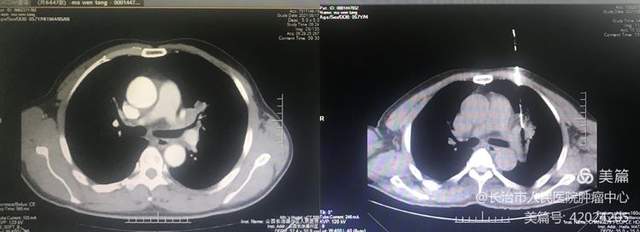

3.韩某,食管癌肝转移,穿刺活检➕粒子植入。

病灶明显缩小,评价PR